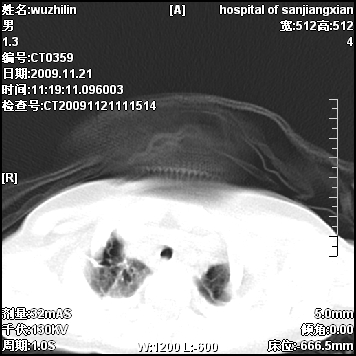

标题: PED3072: 1岁3个月患儿 胸部弥漫性病变 [打印本页]

标题: PED3072: 1岁3个月患儿 胸部弥漫性病变

弥漫性薄壁囊腔,胸膜下及肺底部占优势,双上肺磨玻璃密度影,首先考虑特发性肺间质纤维化,其次囊性肺纤维化,肺淋巴管平滑肌瘤病嗜酸性肉芽肿等;要结合临床综合考虑。

两肺布满多个薄壁含气囊腔,以下肺居多,伴磨玻璃样密度影,左侧气胸。两肺发育不全、两肺多发肺囊肿并感染,其次考虑肺囊腺瘤。